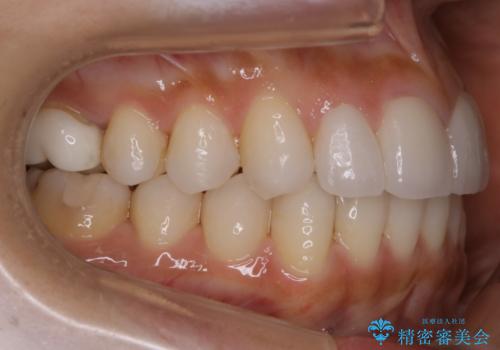

【非抜歯】噛み合わせを整えたい! インビザライン矯正

- 嚙み合わせのズレを主訴にご来院されました。

前歯・奥歯ともにセラミッククラウンで治療されている歯があったため、その歯にあまり影響が出ない範囲内で全体の噛み合わせが良くなるような動きを組み込んで治療を進めることとなりました。